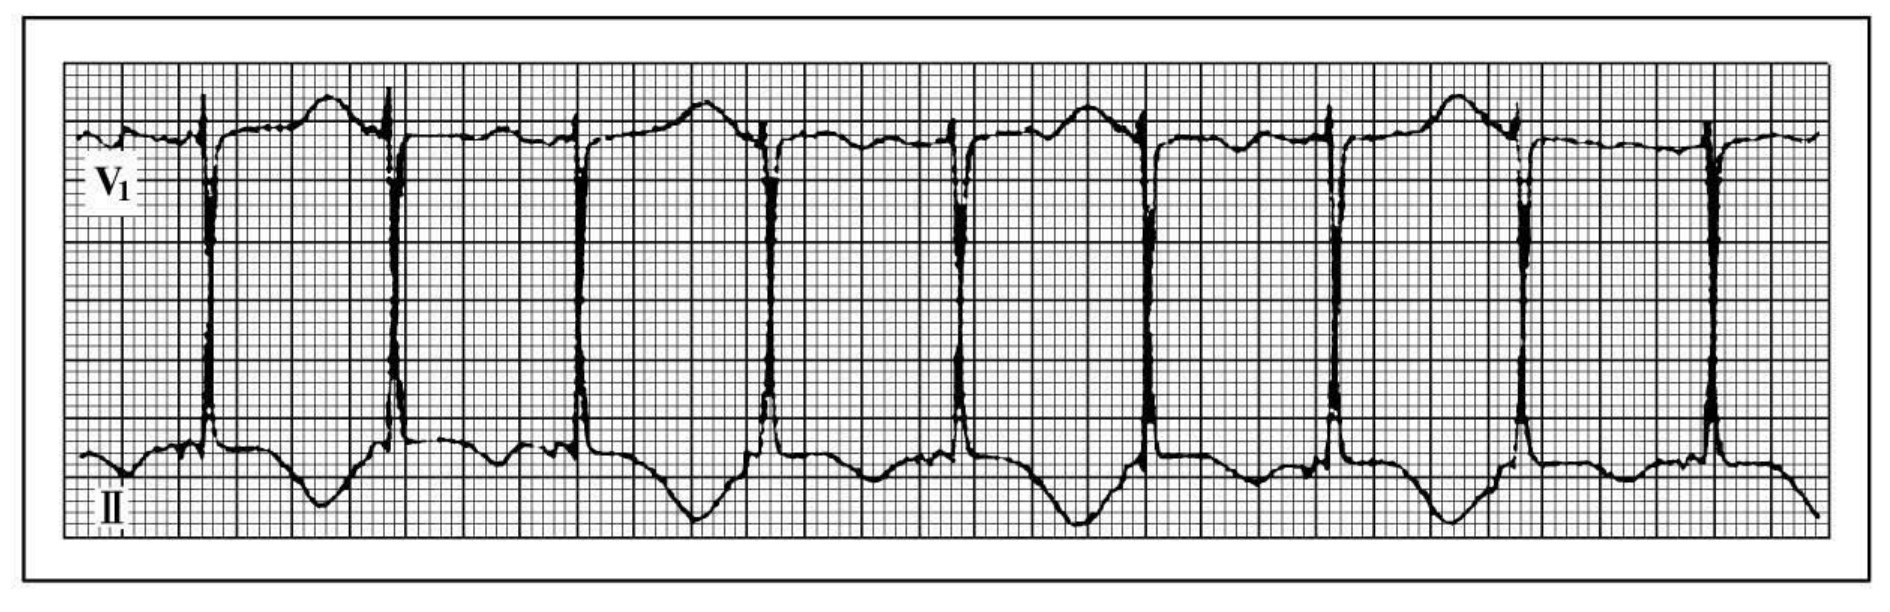

img983

图44-121 T波交替的心电图